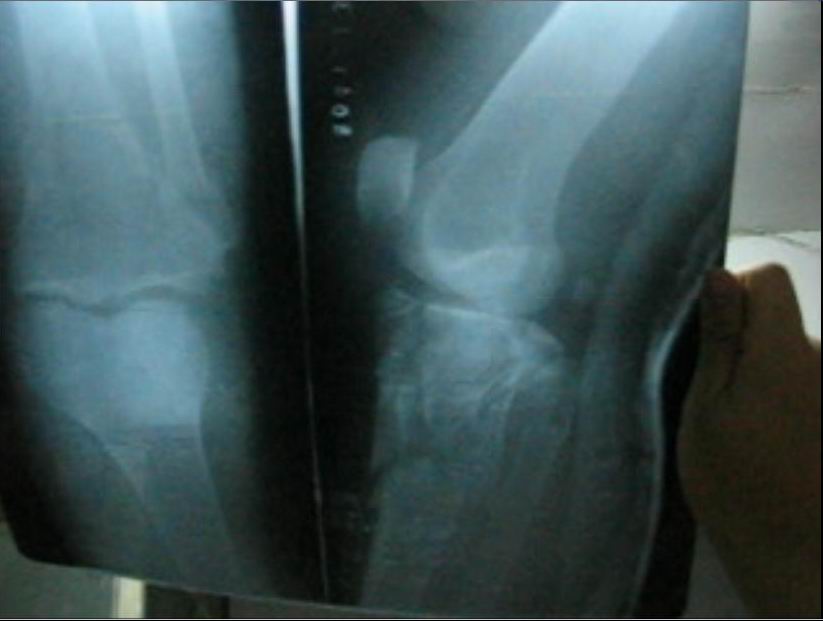

焦龙下来时不慎把左腿摔成粉碎性骨折。被抓后因不能行走,恶警就拽着焦龙的胳膊在地上拖着走,一直拖进车里,他们并没有把他送进医院,而是拉到了团结路派出所,下车时他们还是拽着胳膊在地上把焦龙拖进屋里,并开始对他非法审讯。恶警董某甚至用脚踢他受伤的腿。

而后他们把焦龙送到大庆医院拍片子,拍完后发现多处骨折。从医院他们用车把焦龙拉回派出所,没让他下车。说市里来人正在开会研究,后来出来一位领导模样的人对他说:我们放你走,在大庆有没有亲朋好友,把你接回去治伤。

下面是焦龙的腿摔骨折后的照片。